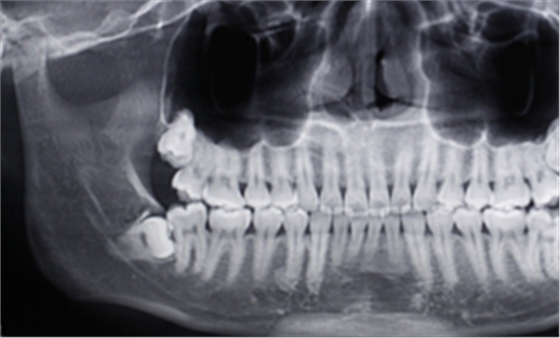

右下智齒去骨范圍如何?分冠線如何?怎樣才能最快時(shí)間能把這顆牙拔出來(lái)?

答:本x線片示48近中低位埋伏阻生,且牙根緊鄰下牙槽神經(jīng)管,拔除時(shí)需注意充分去除近中方向的牙體冠方阻力及遠(yuǎn)中的牙槽骨阻力,挺出牙根時(shí)盡量做到一次完成,減少牙根與神經(jīng)管的摩擦,降低神經(jīng)受損風(fēng)險(xiǎn)。

遠(yuǎn)中:骨阻力 近中:牙體冠方組織

第一:確定阻力去骨的范圍: